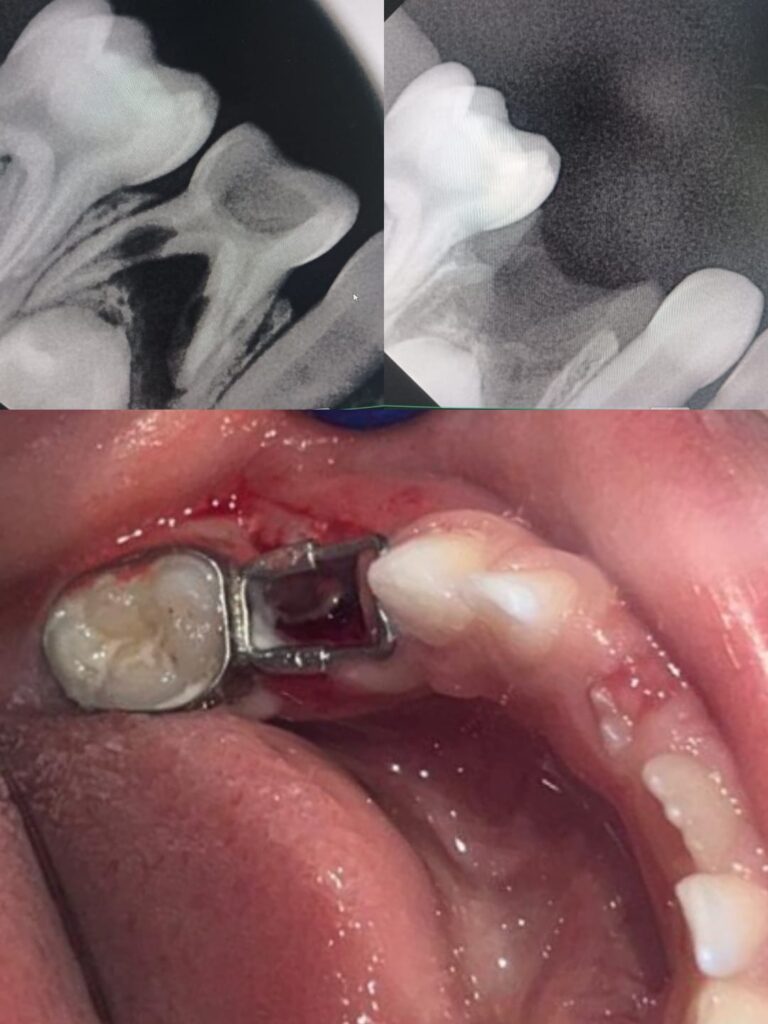

1. Fixed Space Maintainer

This type is cemented to adjacent teeth and cannot be removed by the child.

Common types include:

- Band and loop

- Crown and loop

- Lingual holding arch

These are most commonly used in pediatric dentistry.

How Is a Tooth Space Maintainer Placed?

The procedure is simple and painless.

Step-by-step process:

- Dental examination and X-ray

- Measurement of space

- Custom fabrication

- Fitting and cementation

The entire procedure is comfortable and completed in minimal visits.